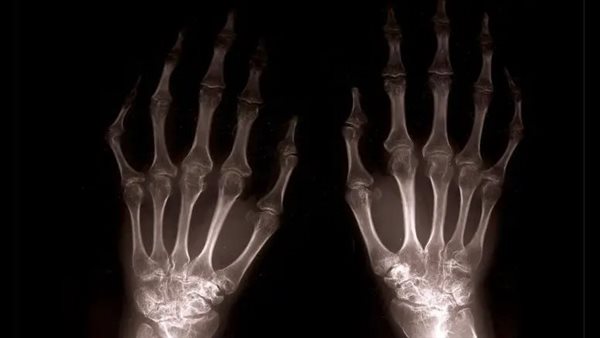

علاج التهاب المفاصل عن طريق أحد الأعشاب الطبية

وبحسب نتائج الدراسة التي نشرت نتائجها في Science Immunology، حدد الباحثون مركبًا بروتينيًا يلعب دورًا في تسريع علاج التهاب المفاصل الروماتويدي، وهذا المركب موجود في جذر نبات طبي يعرف باسم كرمة إله الرعد.